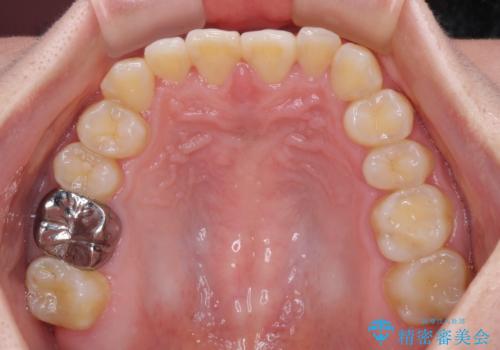

- 矯正装置

- メタルブラケット

- 前歯の反対咬合を気にして来院された患者様です。

当院にて同様の咬み合わせを治療した方からのご紹介ということもあり、ご紹介者と同じワイヤー矯正で早めに治療を終えることを希望されました。

骨格的に下顎が前方に位置していましたが、歯列矯正で改善できると判断し、ワイヤー装置にて矯正治療を行うこととしました。

このような咬み合わせの方の多くは、舌の突出癖が強い傾向にあり、反対咬合改善後に開咬となってしまい、なかなか治療が終わらないことがあります。

こちらの患者様は、舌のトレーニングを治療開始前から徹底的に実践していただき、僅か8ヶ月という短期間で治療を終えることができました。